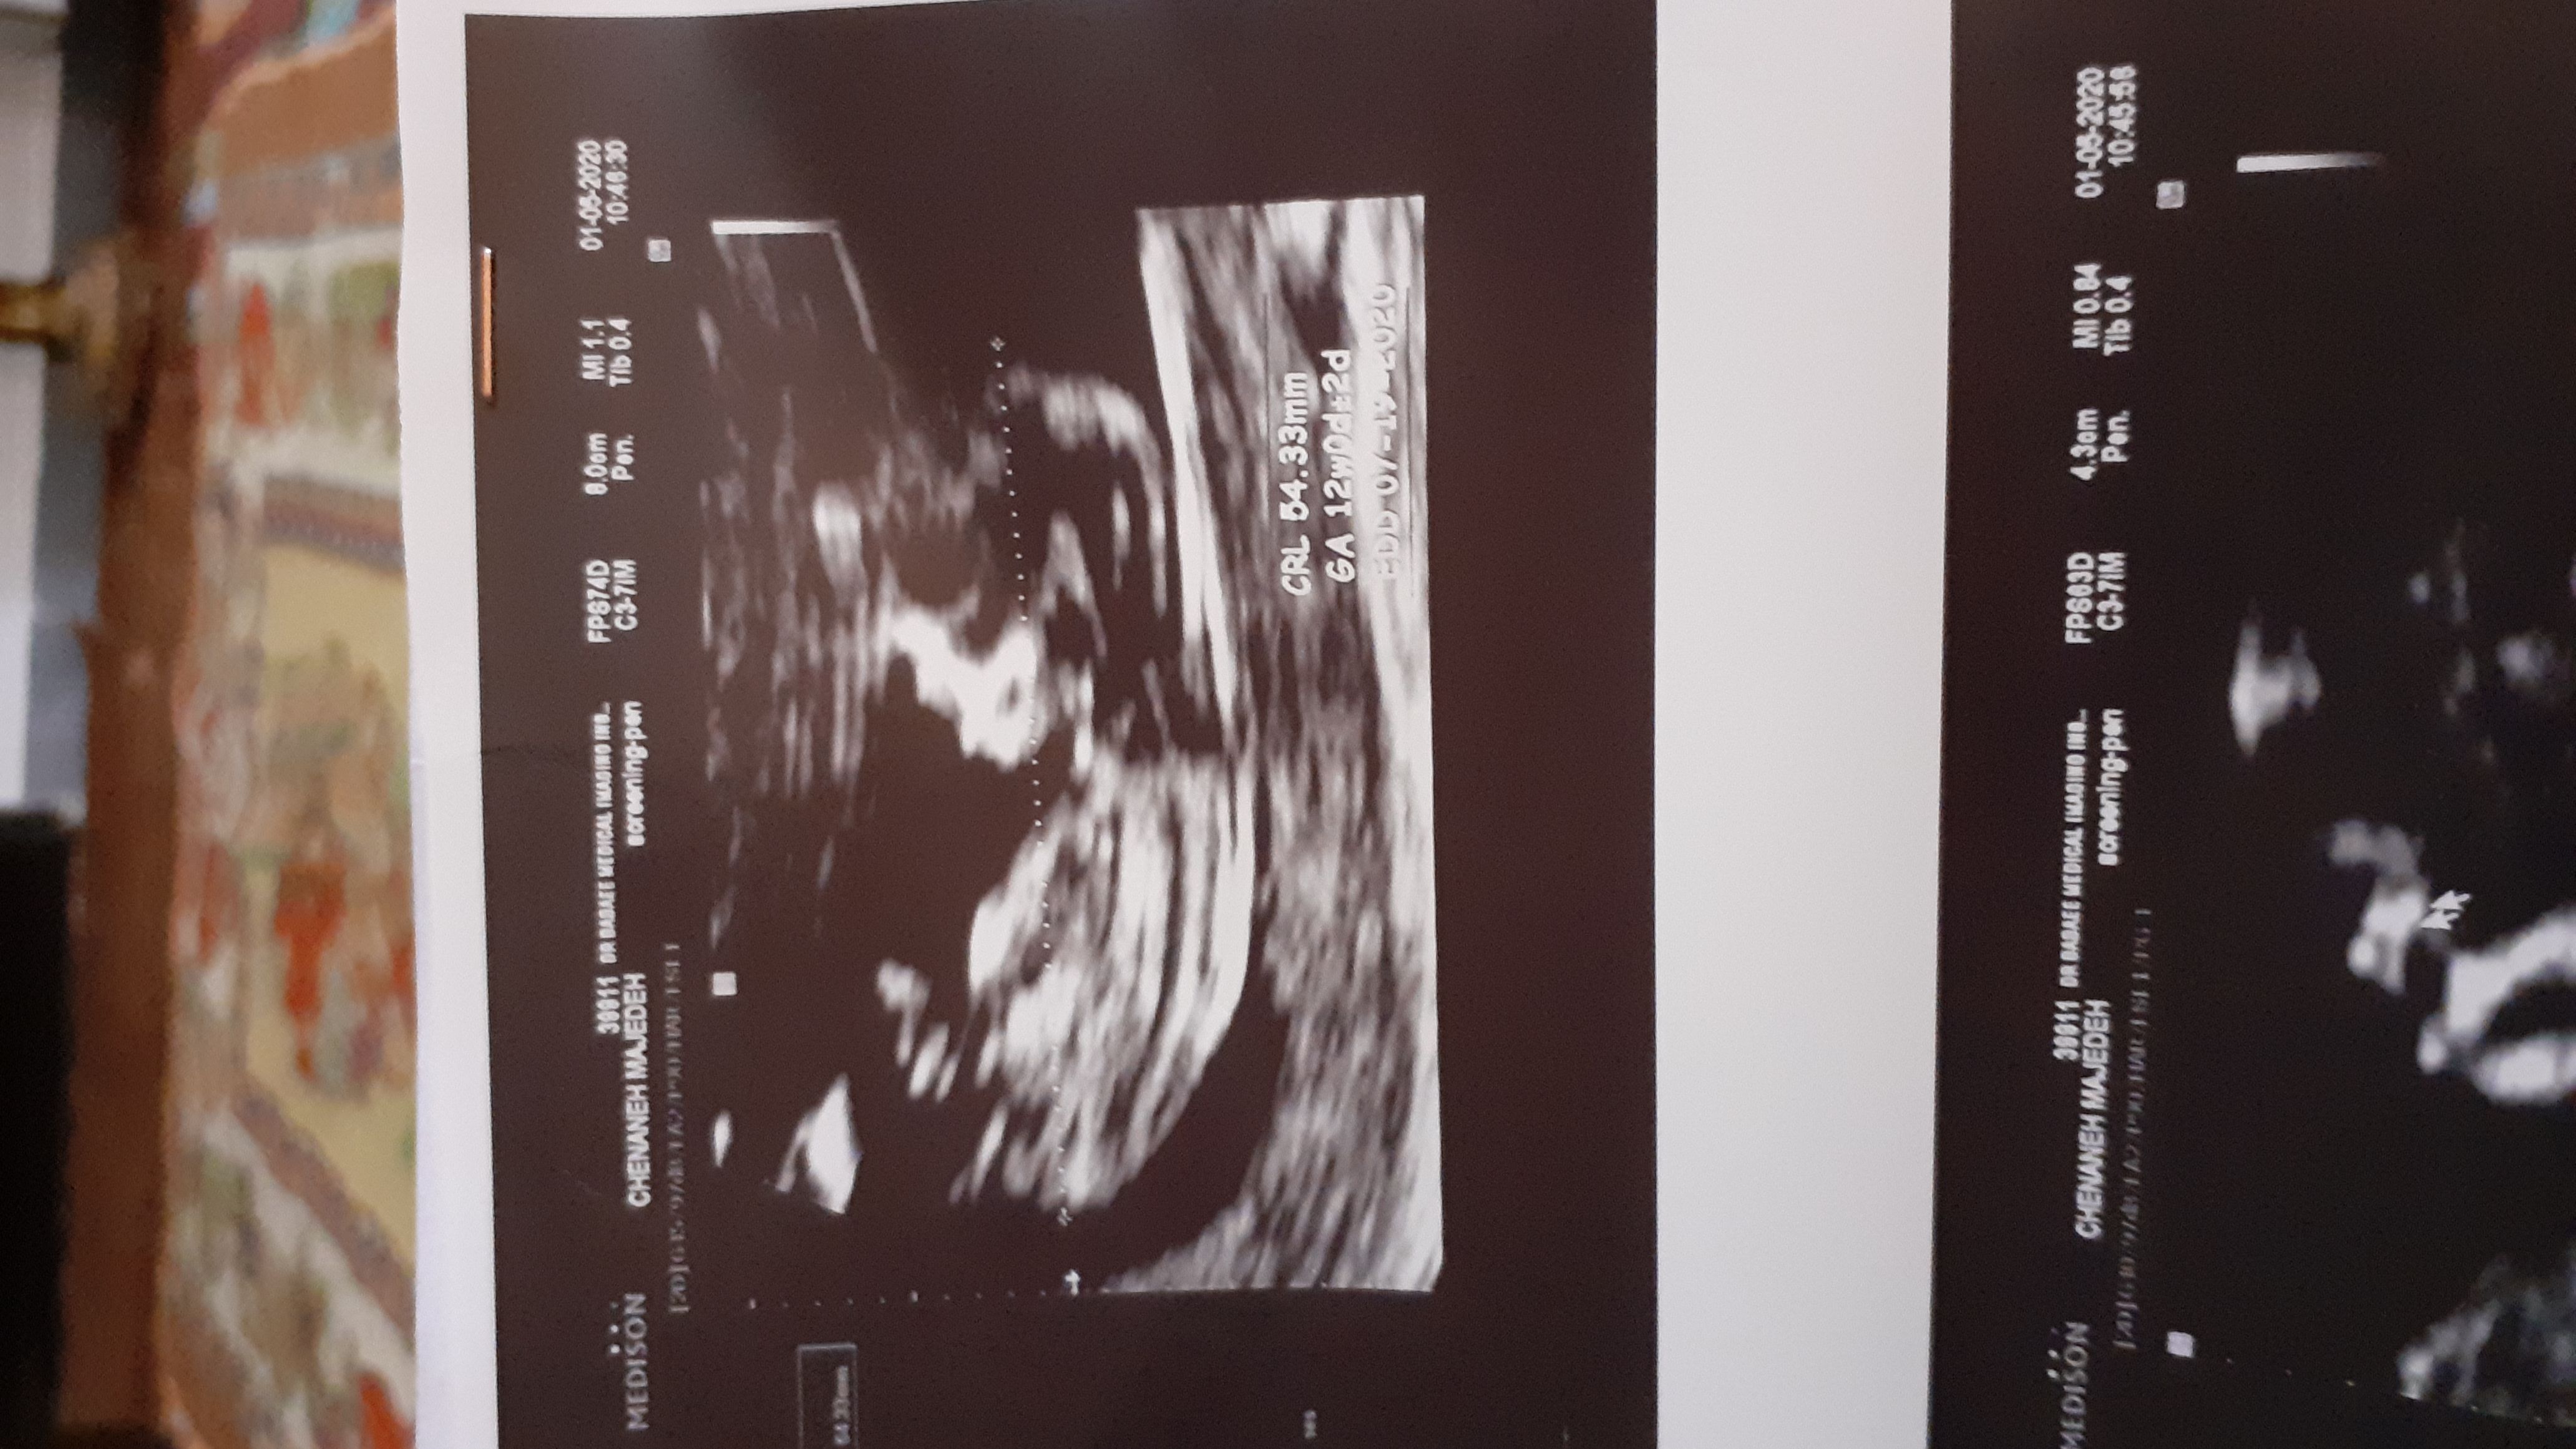

reihane1394 مدیر استارتر عضویت: 1399/03/09 تعداد پست: 796 عنوان کسی بلده ازروی عکس ان تی بگه نی نیم چیه؟؟ 376 بازدید | 25 پست حدس زده دکتراماشک دارم چون هیچ علایمی ندارم 1399/03/24 | 20:05 0 نفر لایک کرده اند ... گزارش تاپیک نامناسب

reihane1394 مدیر استارتر عضویت: 1399/03/09 تعداد پست: 796 نمیدونم سه تانظرداده راجع به نی نیم فک کنم ۱۲هفته و۴روز

reihane1394 مدیر استارتر عضویت: 1399/03/09 تعداد پست: 796 آره گفت احتمالا دختره هیچ علائمی ندارم از حالت تهوع